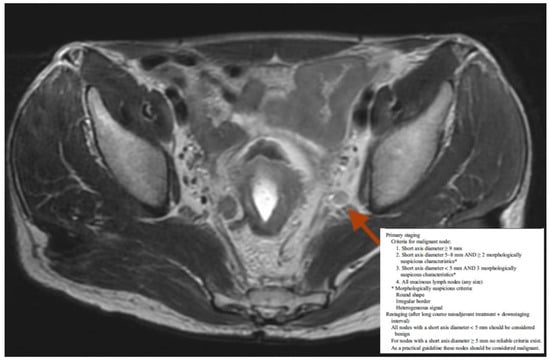

- Beets-Tan, R.G.H.; Lambregts, D.M.J.; Maas, M.; Bipat, S.; Barbaro, B.; Curvo-Semedo, L.; Fenlon, H.M.; Gollub, M.J.; Gourtsoyianni, S.; Halligan, S.; et al. Magnetic Resonance Imaging for Clinical Management of Rectal Cancer: Updated Recommendations from the 2016 European Society of Gastrointestinal and Abdominal Radiology (ESGAR) Consensus Meeting. Eur. Radiol. 2018, 28, 1465–1475. [Google Scholar] [CrossRef]